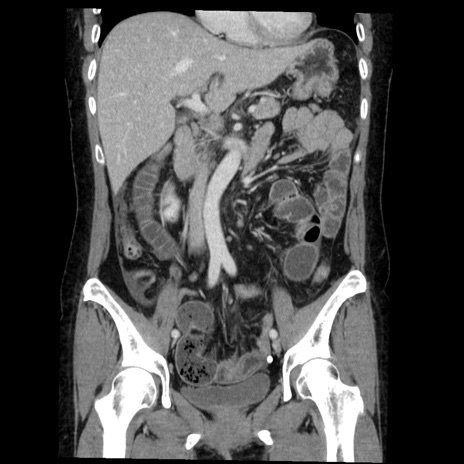

症例6(冠状断像)

【症例】50歳代女性

【主訴】下腹部痛

【現病歴】本日朝より下痢2回あり。 昼食を食べた後、嘔吐3回、下腹部痛認め、症状軽快せず、当院救急搬送。

最終食事:本日昼(生ものなし)。 昨日の夜、刺身を食ぺたとのこと。周囲に同様の症状の者なし。普段、排便は毎日あるとのこと。

【既往歴】卵巣癌術後(8年前に当院で卵巣摘出)

【身体所見】 意識清明、腹部:平坦、腸蠕動音→、やや硬、下腹部自発痛・圧痛あり、反跳痛あり、筋性防御なし。

【データ】WBC 16000、CRP 0.01